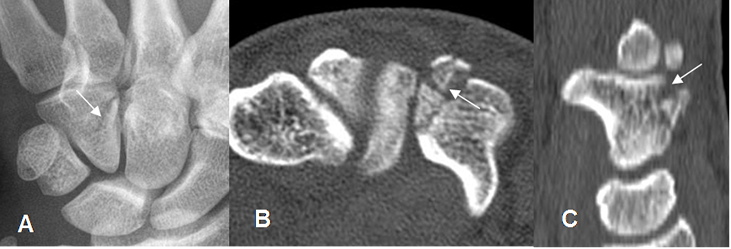

Fig 44 C. Fractura del ganchoso.

A: Rx AP. Fractura oblicua del ganchoso.

B: TAC axial y C: TAC reconstrucción sagital. Fractura conminuta del ganchoso.